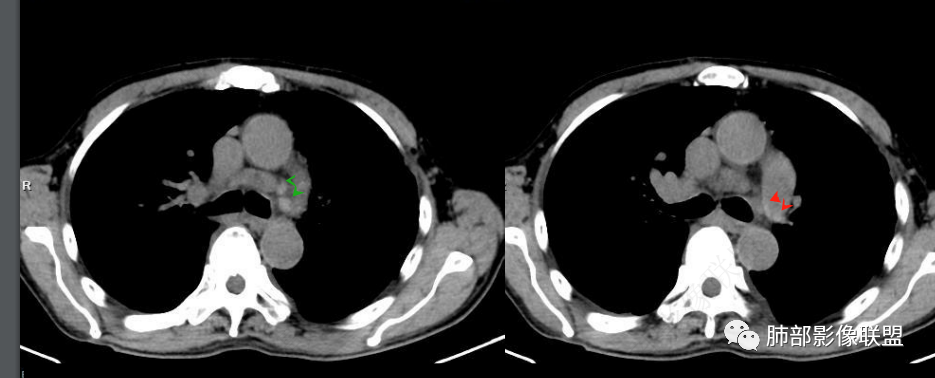

看一下影像,肺动脉粗大,大于升主动脉

6.心脏影增大,右房室增大为主。(增强:左心房及肺静脉入口见充盈缺损)

7.肺动脉主干扩张,左侧肺动脉主干见混杂密度影,上下肺动脉似不能连续追踪。

(增强:左肺动脉充盈缺损、闭塞)

2.影像右侧肺水肿提示左心回流障碍。左心房及肺静脉入口见充盈缺损提示血栓存在。

3.影像胸壁迂曲扩张静脉血管提示右心回流障碍(可呼应双下肢浮肿)。

4.心脏影增大;肺动脉高压。

5.影像左肺动脉栓塞、闭塞——上下肺动脉以远相对纤细——左肺动脉“断供”,且存在支气管动脉扩张可能。